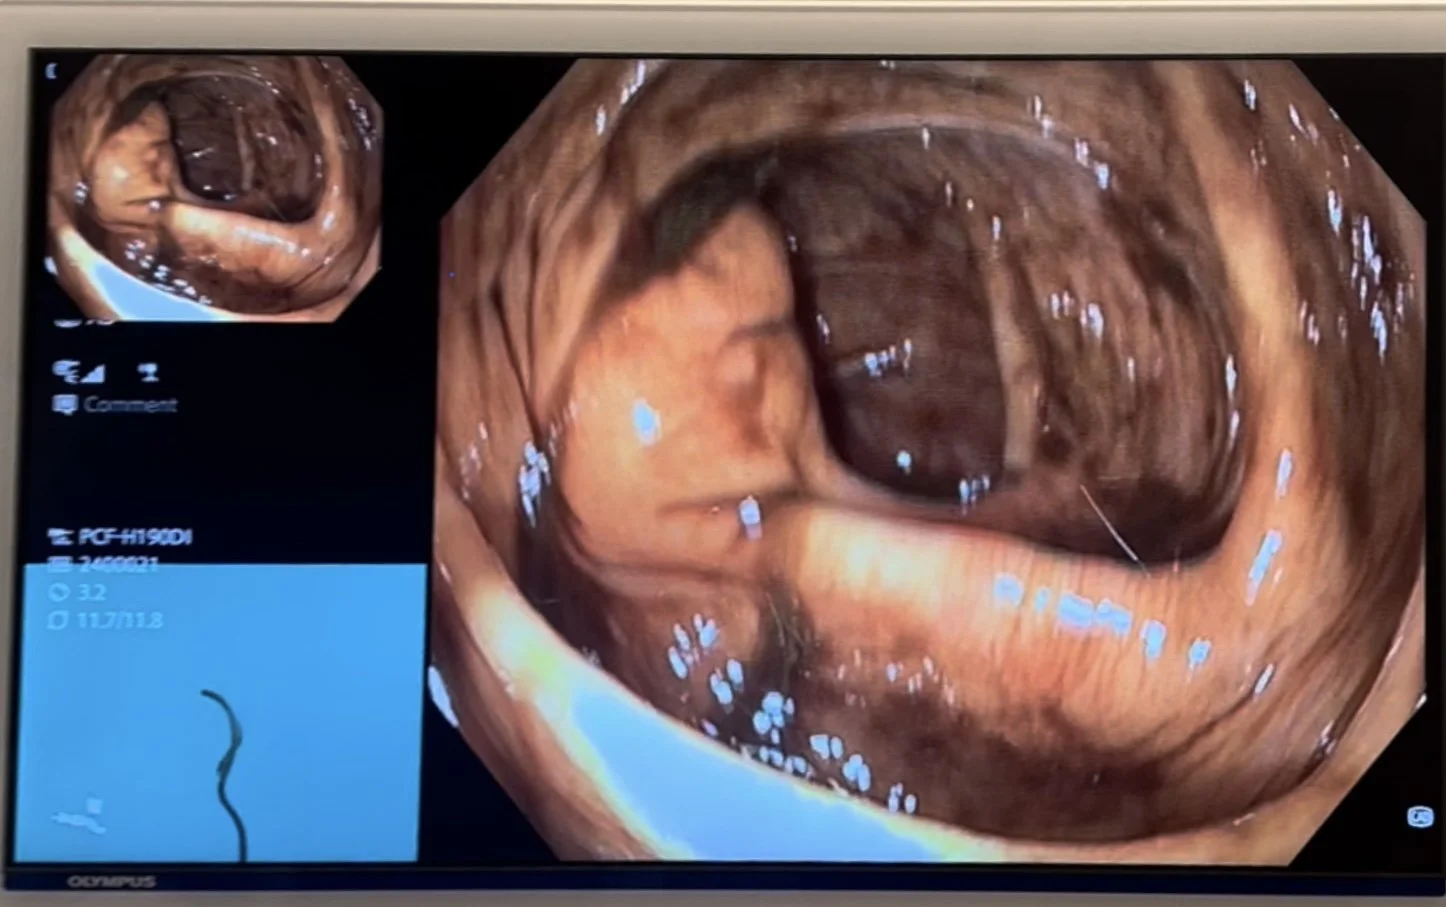

Først litt om utstyret. Det er flere produsenter av koloskop, med de er i prinsippet bygget opp likt. Det er en gummislange på omtrent 140cm. Tuppen av gummislangen har lys og et lite kamera. Kameraet har fantastisk optikk og gjerne 4K kvalitet på videobildene som genereres. På tuppen er det en spyl og sug åpning, en linsevasker og en arbeidskanal. Gjennom arbeidskanalen kan legen sette inn utstyr for å ta vevsprøver, fjerne polypper og annen sykdom og det kan settes inn klyper og nett for å ta med seg vevsprøver. Lyset i tuppen av koloskopet kan endre farge, slik at vev som har syke karområder eller endret struktur vises bedre. Tuppen på kolskopet kan vrie til høyre/ venstre og opp/ned. På den måten kan koloskopet sikte seg inn mot åpningen i tykktarmen og føres inn uten å skade slimhinnen. Legen som utøver undersøkelsen kan sette inn gass og vann, eller suge det ut. Avhengig av hvor man er i tarmen, vil undersøkeren gjerne ha litt mer eller mindre tyngde i tarmen, for å letter komme forbi svinger. Et hjelpemiddel som ofte er tilgjenglig er en “Skop-guide”. Det er en detektor som ved hjelp av magnetisme og avanserte databeregninger klarer å vise hvordan koloskopet ligger i buken. Moderne koloskop har egen programvare med kunstig intelligens, slik at alle områder i tarmen også blir vurdert av en dataprosessor.

Man kaller undersøkelsen for koloskopi, men man ser bare slimhinnen. Noen ganger kan man få inntrykk av om det er forandringer i den muskulære veggen av tykktarmen, eller om det er sykdom i bukhinnen som kler tykktarmen. Dette kan man sjelden observere visuelt. Det er indirekte observasjoner, ved at slimhinnen i tarmen buker inn eller ut på steder den ikke skal gjøre det, eller ved at man kommer til knekk dannelser i tarmen som ikke burde være der.

Under en koloskopi kan legen påvise medfødte misdannelser, karforandringer, fargeforandringer, betennelser, innvollsorm, utposninger, polypper og kreft. Dersom legen påviser sykdom tidlig, kan den nesten alltid kureres.